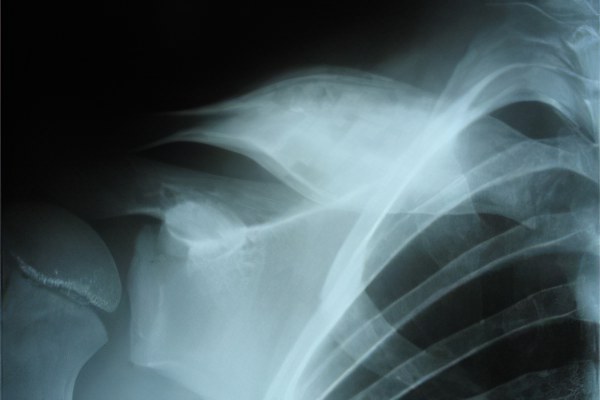

На рентгеновских снимках и результатах компьютерной томографии четко видны чередования здоровых участков тканей с зонами повреждений различной формы и размеров.

Для диагностики используются рентгенографические исследования, которые могут выявить изменения уже на 12–14 день после завершения острого периода. На этом этапе особенно полезен метод фистулографии, представляющий собой компьютерную томографию с контрастным веществом. Четкое изображение позволяет точно определить размеры секвестров, их расположение и степень выраженности заболевания.

- Рентгенография — наиболее распространенный метод диагностики остеомиелита. С помощью рентгеновских снимков можно определить локализацию некротических процессов, объем и степень выраженности инфекционного очага. Рентген позволяет выявить заболевание на ранних стадиях, а по мере прогрессирования воспаления изменяется характер изображений, что помогает точно определить время течения болезни.

- Компьютерная томография — наиболее информативный метод диагностики остеомиелита в любых его формах. Объемные изображения предоставляют данные о локализации и интенсивности инфекции, а также позволяют создать реконструкцию окружающих мышечных тканей и спрогнозировать течение заболевания.